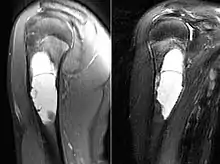

MRI scan: simple bone cyst humerus of a 13 year old boy

Magnetic Resonance Imaging (MRI)

Magnetic resonance imaging scans are used to identify the precise location of the cyst, to see how aggressive the disease is, and to determine the actual shape and size.[4] The MRI uses a combination of magnets and radio-frequencies to produce various detailed, computerized images of the cyst and its surrounding body structures.[4]